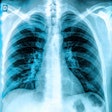

Can radiographer reporting play a wider role in lung cancer?

Investigation reveals how stressed radiologist missed cancer